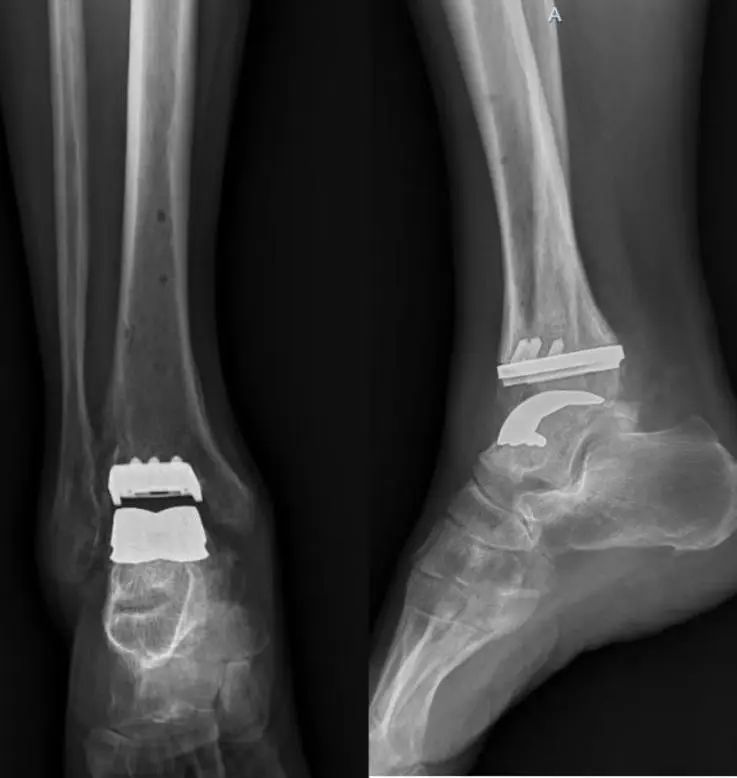

近日,西南医科大学附属医院骨科与运动医学中心成功为饱受双侧踝关节炎折磨多年的患者舒大爷完成川南地区首例双侧Infinity人工踝关节置换手术。术后患者恢复良好,双侧踝关节功能显著改善。

半年后,舒先生满怀信心再次入院,要求对左侧踝关节实施同类型手术。经过周密的术前规划,足踝外科团队凭借娴熟的技术,仅用2小时顺利完成手术。术后影像显示假体位置精准,关节力线完美恢复。目前,舒大爷已能自主进行康复训练,双踝活动自如,重拾生活信心。